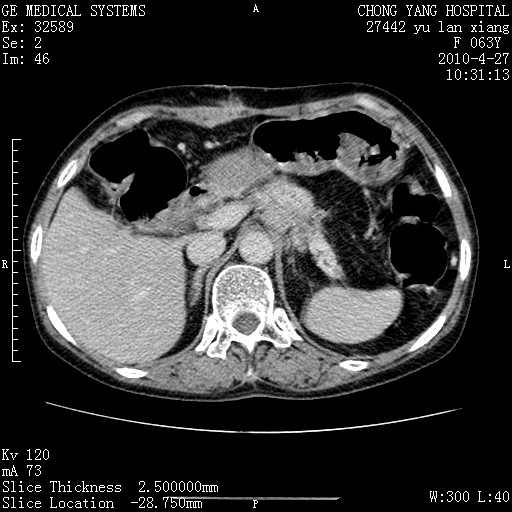

标题: CT26066:F63Y 上腹正中压痛半月,CA199:7400u/ml,MR示胰腺炎伴 [打印本页]

胰腺癌侵犯腹腔动脉干-分支、胃壁、左侧膈肌伴胰周及腹膜后淋巴结转移、胆囊切除术后。

胰腺癌侵犯腹腔动脉干-分支、胃壁、左侧膈肌伴胰周及腹膜后淋巴结转移、胆囊未显影。